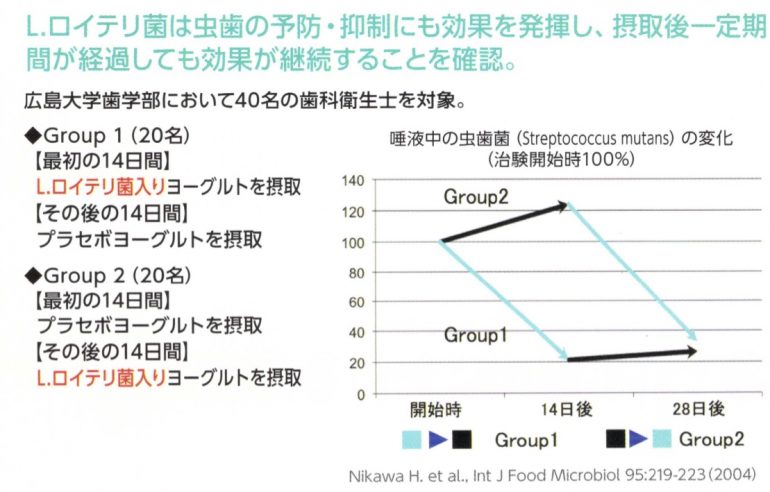

むし歯の原因菌を減少させる

2週間連続で摂取することで、むし歯の原因菌を約80%も減少させます。